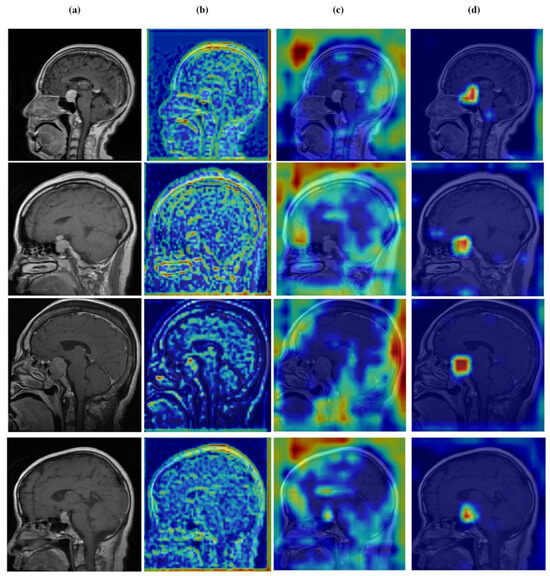

Figure 12, Figure 13, Figure 14 and Figure 15 present Grad-CAM visualizations that trace the hierarchical feature learning of the proposed model across the four classes. Columns are organized as (a) input, (b) high-level features, (c) mid-level features, and (d) low-level features. In (d), the network emphasizes primitive cue edges, intensity transitions, and fine textures capturing sulcal boundaries, skull edges, and generic tissue patterns. Progressing to (c), activations become more structured and context-aware, highlighting coherent anatomical regions and diffuse hyperintense areas that provide spatial context for lesion localization. At (b), class-discriminative focus emerges with responses that contract tumor-centric hotspots for glioma and meningioma and to the sellar region for pituitary cases, while no_tumor images exhibit suppressed high-level responses, reflecting the model’s rejection of false lesion cues. This bottom-to-top progression from generic edges to task-specific evidence explains the model’s improved decision reliability and aligns with the multi-task design that encourages precise, clinically meaningful attention.

Figure 12.

Visual representation of feature activations in no tumor cases. (a) input, (b) low-level features, (c) mid-level features, and (d) high-level features.

Figure 13.

Visual representation of feature activations in glioma tumor cases. (a) input, (b) low-level features, (c) mid-level features, and (d) high-level features.

Figure 14.

Visual representation of feature activations in meningioma tumor cases. (a) input, (b) low-level features, (c) mid-level features, and (d) high-level features.

Figure 15.

Visual representation of feature activations in pituitary tumor cases. (a) input, (b) low-level features, (c) mid-level features, and (d) high-level features.